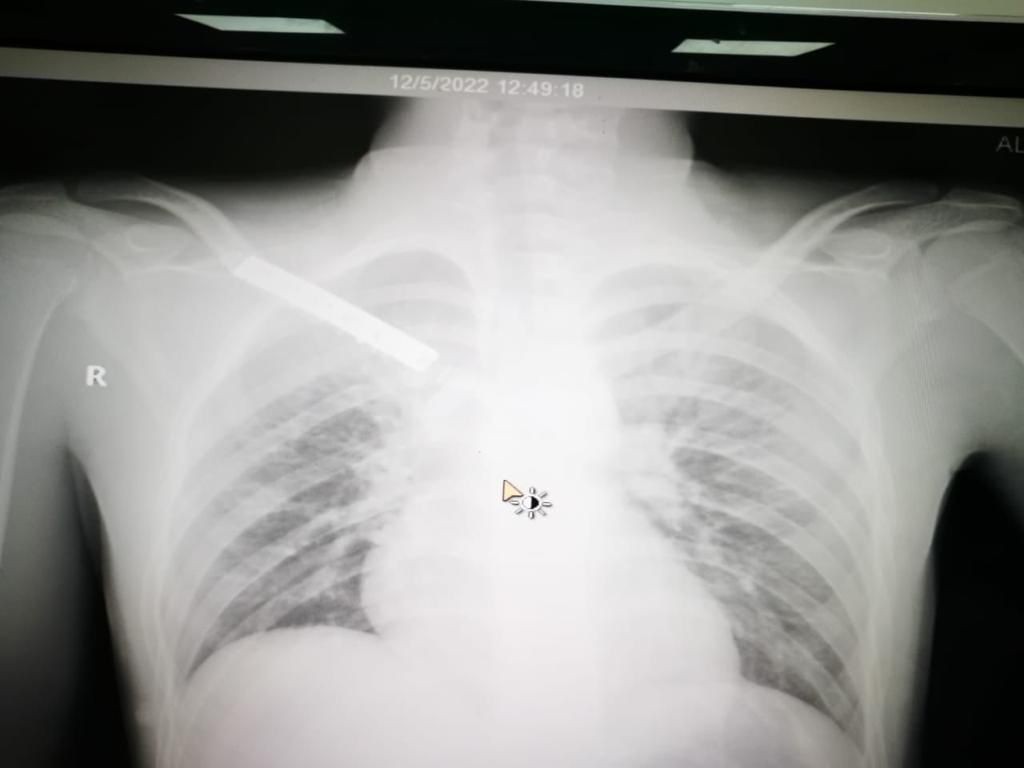

تمكن فريق طبي في منطقة تبوك من إجراء عملية دقيقة ومعقدة لإرجاع عظم الترقوة والقفص الصدري إلى مريض تعرض لحادث مروري إستغرقت مدتها 4 ساعات تكللت ولله الحمد بالنجاح. وقالت صحة تبوك إن أطباء مستشفى الملك خالد في منطقة تبوك تمكنوا ولله الحمد من إنقاذ حياة شاب وصل لقسم الإسعاف بحالة حرجة نتيجة تعرضه لحادث مروري فقد بسببه كميات كبيرة من الدم جراء النزيف الذي فقده الجسم ، وتم تقديم الإسعافات الطبية الأولية العاجلة لإيقاف النزيف. وأكدت أنه بعد إجراء الفحوصات السريرية والإشعاعية والمخبرية تبين وجود انفصال تام لعظم الترقوة مع عظم القفص الصدري بالإضافة إلى كدمات في الرئة وكسور في عظام الحوض وخلع في المفصل مما استدعى دخوله بشكل عاجل لغرفة العمليات الكبرى وإجراء عملية أمامية على الصدر شملت المفصل القصي الترقوي وعظم الترقوة اليمنى مترادفات وإزالة الضغط على القسم العلوي من الرئة والشريان والأوردة والأعصاب التي تغذي الطرف العلوي وتفريغ التجمع الدموي الناتج عن الخلع والكسر وإعادة الجزء المكسور من الترقوة من داخل القصي والربط بين الضلع الأيمن الأول والترقوة للمحافظة على ثبات المفصل، حتى استقرت الحالة لتنقل بعدها إلى غرف التنويم لاستكمال المتابعة الطبية لها حتى الخروج من المستشفى- بإذن الله- بصحة جيدة. يذكر أن مستشفى الملك خالد خلال ال (3) الأشهر الماضية أجرى أكثر من 1031 عملية منها 381 عملية طارئة و 650 عملية روتينية.